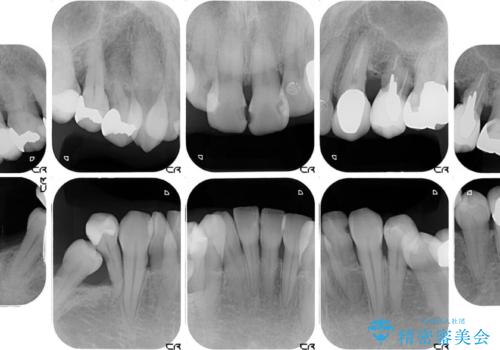

奥歯は咬み合わせや歯周病により歯槽骨が失われていたり、むし歯や破折している歯などがあったりと、歯周病治療やインプラント補綴、矯正治療など、総合的に治療が必要と診断されました。

まずは歯周病治療やインプラント埋入を行い、環境が整った後にワイヤーを併用したインビザライン矯正を行い、オールセラミッククラウンにて補綴治療を行うこととしました。